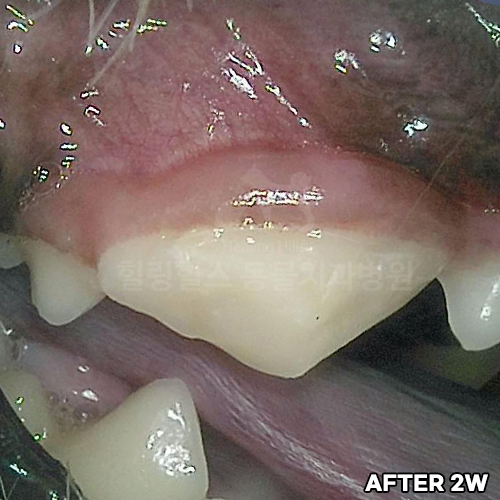

[심한 치아파절 자기치아파편으로 치아살리기]

샘플 샘플